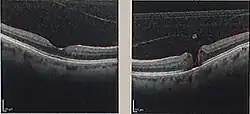

Optical coherence tomography (OCT) of a macular hole (right) as compared to a normal macula.

A macular hole is a small break in the macula, located in the center of the eye's light-sensitive tissue called the retina.